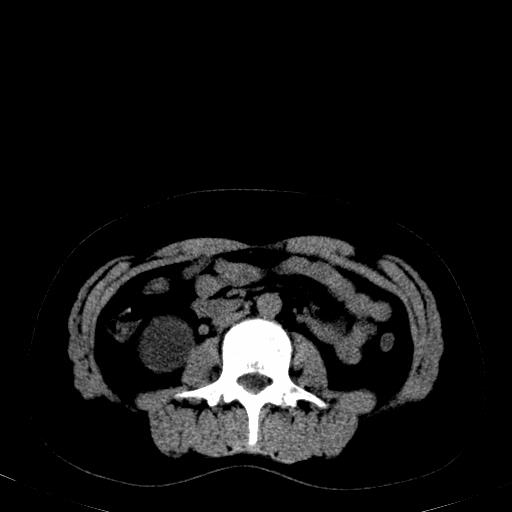

患者体检发现右肾体积增大,怀疑右肾积水

右肾重度积水,以肾盏积水明显,有分隔,上段输尿管轻度扩张,管壁增厚,考虑肾结核可能,请结合尿检查,胸部拍片排除肺结核。

右肾重度积水,建议ct向下扫描或逆行造影,左肾及左输尿管结石 .

右侧肾积水、左侧肾结石 ,原因待查

要排除右肾结核可能